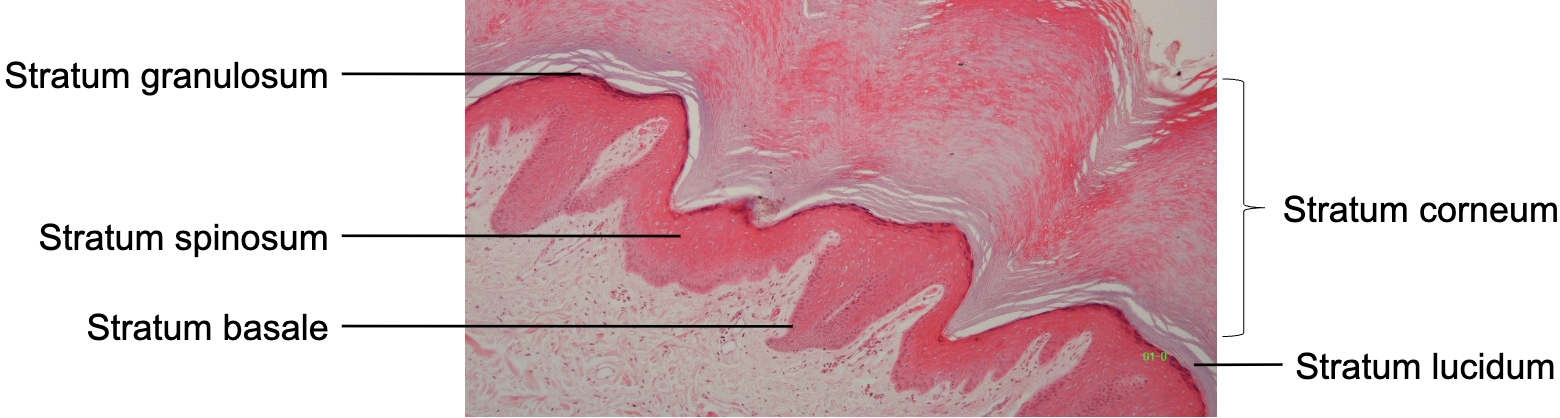

Label strata of epidermis

Thick skin: Strata of epidermis